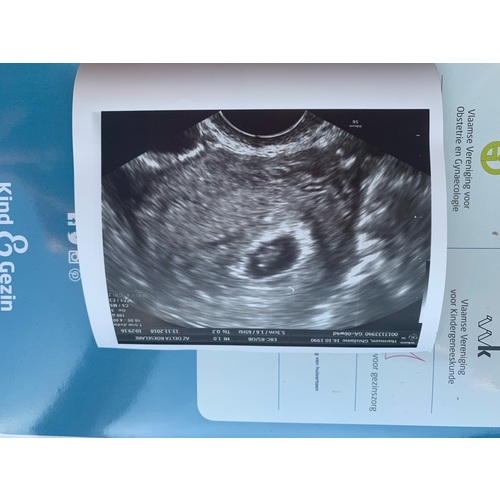

6 weken met kloppend hartje